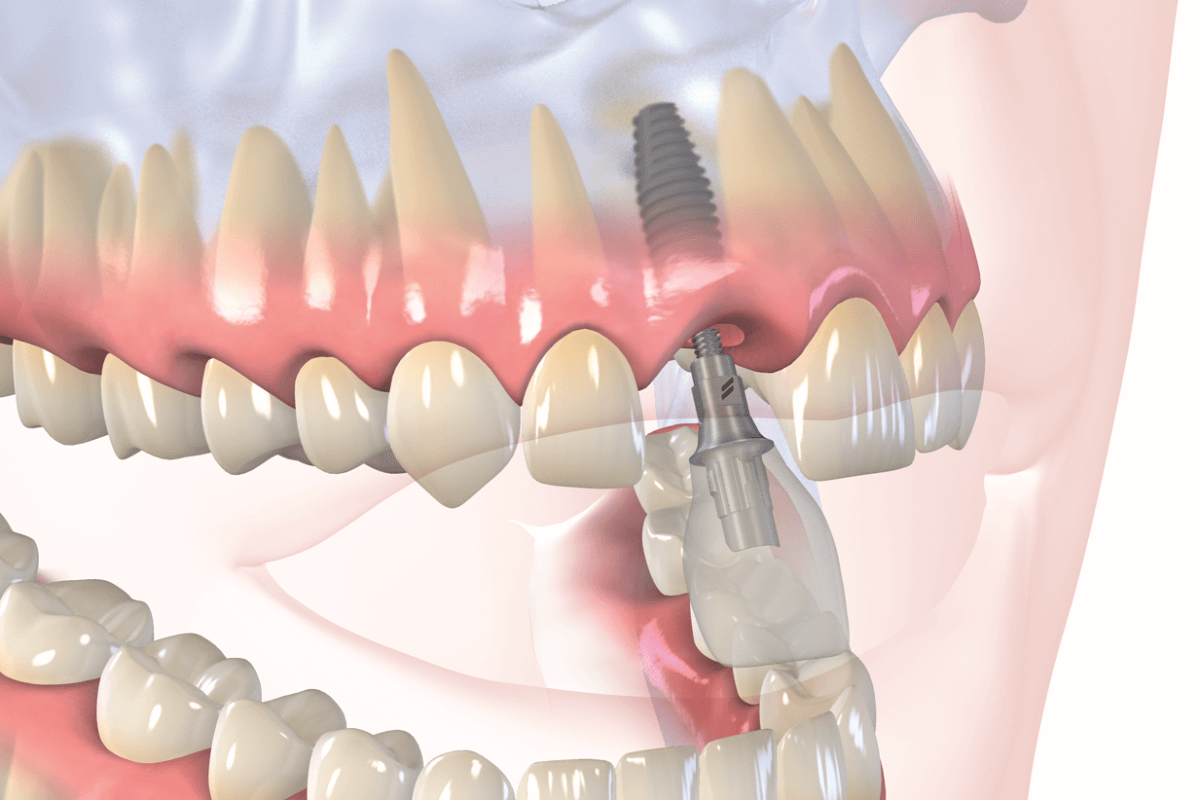

Современная стоматология: Железные зубные импланты